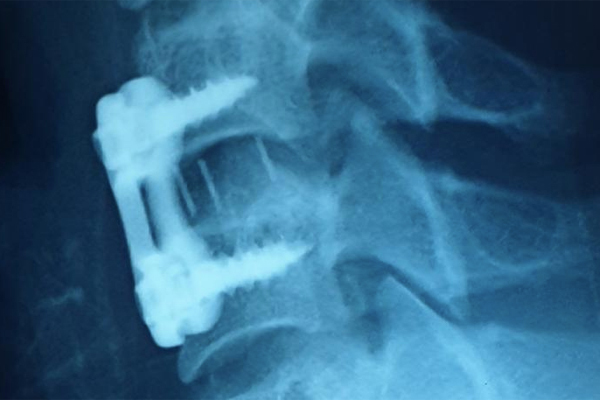

Độc quyền ở Việt Nam: ‘Thước ngắm phẫu thuật’ in 3D giúp thay khớp gối chính xác, an toàn

Một hệ thống định vị trong phẫu thuật khớp gối thiết kế riêng cho từng bệnh nhân vừa được ứng dụng thành công nhờ công nghệ in 3D, giúp ca mổ đạt độ chính xác gần như tuyệt đối; giảm biến chứng sau mổ, tăng tuổi thọ khớp nhân tạo.